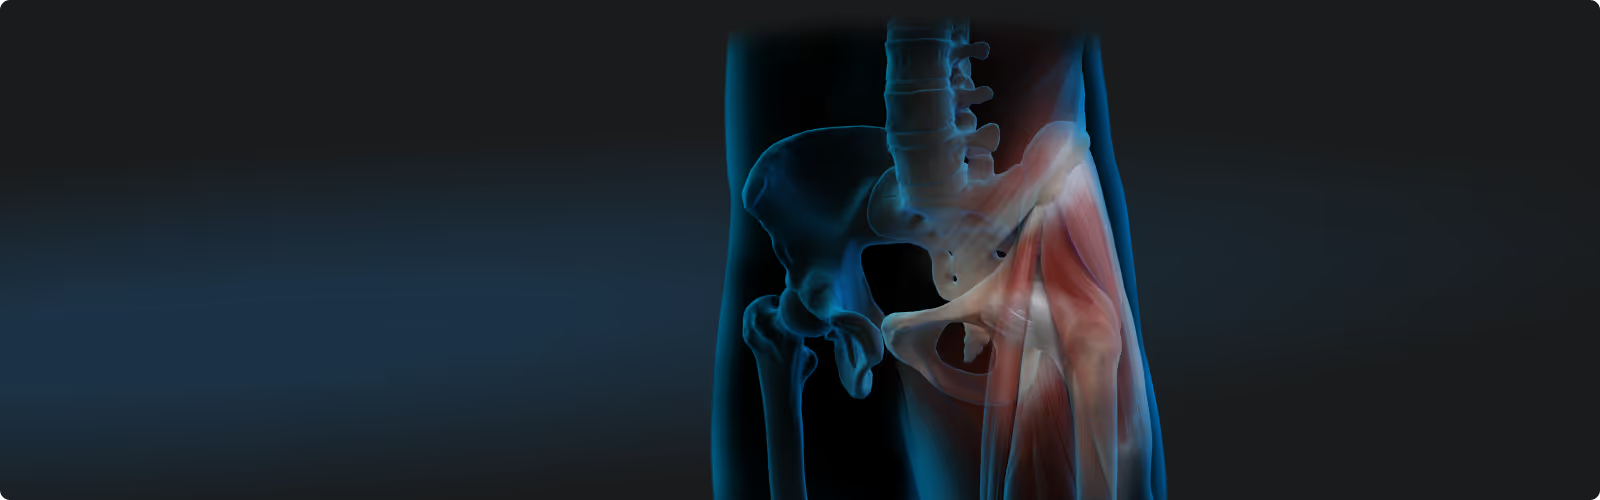

Select your application area and learn how to support your patients' recovery at the cellular level: